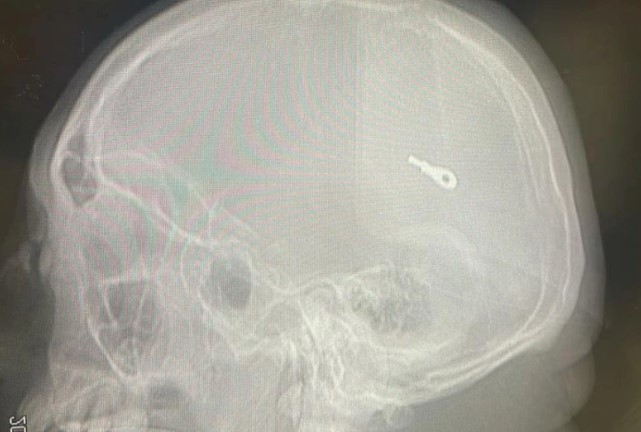

지난 19일(현지 시간) 영국 더 선은 40세 페루 남성이 이달 초 타라포토의 한 병원에서 성형수술을 받은 뒤 사망했다고 보도했다. 코 성형을 위해 해당 병원을 찾은 남성은 수술 후 인근 병원으로 이송돼 추가 검사를 받았으며, 뇌에 작은 수술 기구 조각이 박힌 사실이 확인됐다. 남성은 뇌에 치명적인 손상을 입었고, 뇌사 판정 후 치료를 받던 중 사망했다.